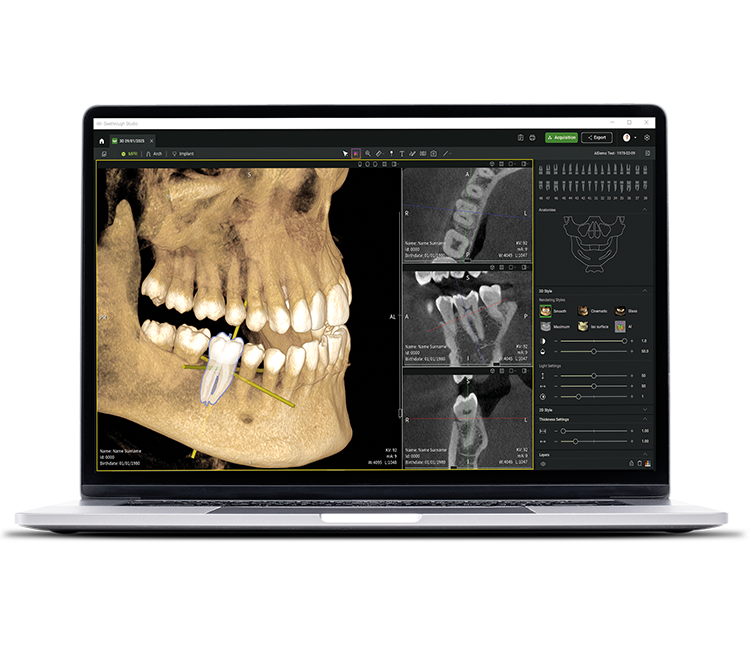

• Seethrough Studio

See tomorrow. See a new level.

Insieme alle tecnologie hardware di ultima generazione, Seethrough Studio rappresenta l'elemento rivoluzionario e differenziante del portfolio imaging W&H. Con funzioni avanzate e algoritmi intelligenti, Seethrough Studio offre un'esperienza all-in-one che spinge verso nuovi orizzonti la qualità dell'imaging e l'efficienza dei workflow digitali.

Integrazione completa

Seethrough Studio può essere facilmente integrato in qualsiasi sistema di gestione dei pazienti. È possibile avviarlo direttamente dal software gestionale senza dover inserire nuovamente i dati del paziente.

Selezione libera del FOV sulle immagini scout

Cattura l'immagine perfetta al primo tentativo: seleziona il FOV nelle preview scout e definisci liberamente la grandezza della regione di interesse. La speciale funzione di selezione libera del FOV direttamente dalle immagini scout garantisce alta precisione evitando di dover ripetere l'esame.

Correzione del movimento e della posizione del paziente

L'avanzato algoritmo di correzione del movimento del paziente eleva la qualità dell’immagine a nuovi livelli, sia nell'imaging 3D che 2D. Le immagini 2D sono ulteriormente migliorate da un sistema di autofocus a 21 strati integrato nella funzione automatica di correzione della posizione del paziente.

Rimozione degli artefatti metallici (MAR)

Ripristina l'integrità dell'immagine rimuovendo gli artefatti metallici; è possibile esaminare le immagini con o senza funzionalità MAR, per una visualizzazione flessibile e una migliore precisione diagnostica.

Immagini nitide, dettagliate

e prive di distorsioni grazie agli avanzati algoritmi di Seethrough Studio.

Sistema integrato di pianificazione dell'impianto

Oltre all'eccezionale qualità delle immagini e al funzionamento intuitivo, Seethrough Studio offre numerose funzioni utili, come la funzione integrata di pianificazione implantare: una soluzione semplice, precisa e facilmente consultabile.

IA - Intelligenza Artificiale

Seethrough Studio utilizza diversi strumenti di intelligenza artificiale per ottenere immagini ancora migliori, come l'allineamento dei volumi 3D, la segmentazione dei denti, la generazione di linee d'arcata e il riconoscimento automatico del nervo. Inoltre, offre un utile supporto per l'identificazione di patologie.